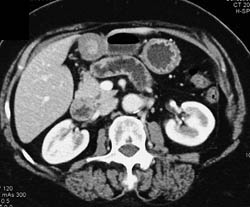

Canada Cronkite Stomach With Multiple Polyps